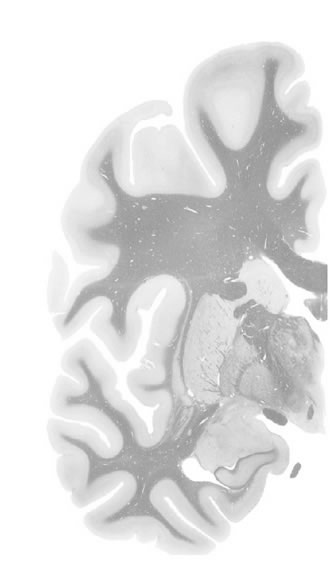

Hi-Resolution Sections · Cells (Nissl Staining) · Virtual Microscopy

Frontal sections (Nissl) from the Atlas Brain:

Macroscopy

Slice ID:

r3-1082

Plate NR:

ca 28-29

Position:

8,5 mm